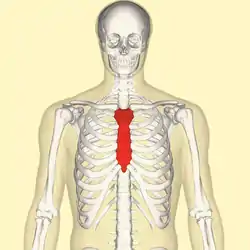

Position of the sternum (red) | |

The sternum (pl.: sternums or sterna) or breastbone is a long flat bone located in the central part of the chest. It connects to the ribs via cartilage and forms the front of the rib cage, thus helping to protect the heart, lungs, and major blood vessels from injury. Shaped roughly like a necktie, it is one of the largest and longest flat bones of the body. Its three regions are the manubrium, the body, and the xiphoid process.[1] The word sternum originates from Ancient Greek στέρνον (stérnon) 'chest'.

Position of sternum (shown in red). Animation.